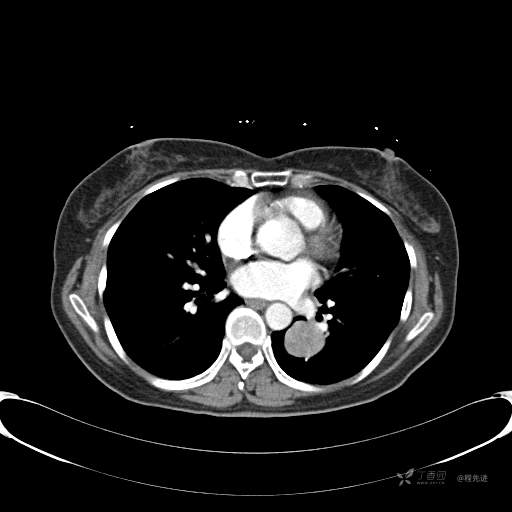

CT增强

平扫CT值约40HU(未上传图像),增强后动脉期CT值约70HU,静脉期CT值约97HU。